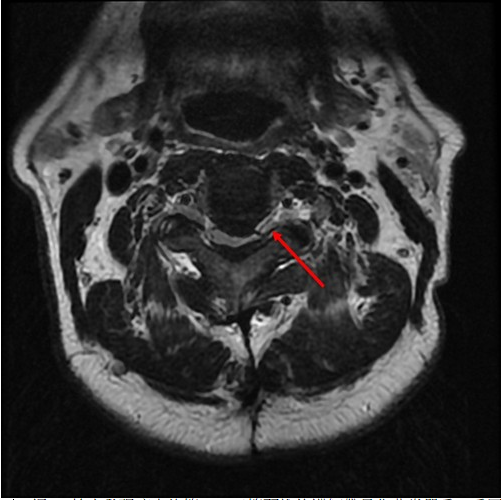

圖:經MRI檢查發現病人的第二、三節頸椎後縱韌帶骨化非常嚴重,受壓迫的神經幾乎扁成一條線。

圖:術前檢查,高位頸椎後縱韌帶骨化,嚴重擠壓脊髓神經(如圖1);醫師精準的用電鑽把骨刺全部磨乾淨,再以骨釘固定及骨融合手術(如圖2)。